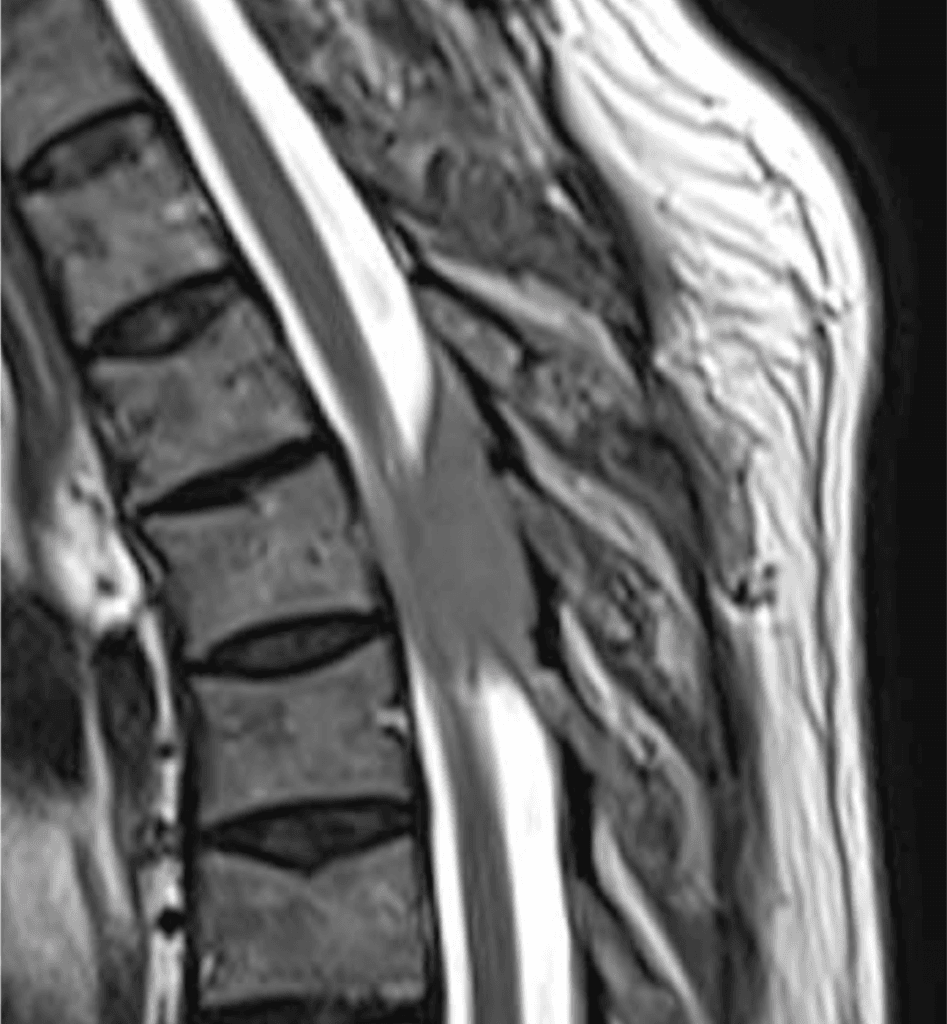

Tumor benigno intra raquídeo extradural e inestabilidad degenerativa asociada

Lumbocruralgia. Dolor lumbar axial, mecánico, progresivo e invalidante. Constante, en posición de pie y acostada, nocturno y diurno.